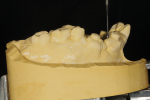

For diagnostic purposes, the prosthodontist mounted diagnostic casts on a semi-adjustable articulator (Stratos 300, Ivoclar Vivadent, ivoclarvivadent.com) with a centric relation record from a Gothic arch tracing device (Massad Jaw Relator, LeeMark Dental, leemarkdental.com) (Figure 5). Additionally, in order to investigate the influence of the facial trauma on the patient's condyles, the prosthodontist performed a computerized mandibular movement analysis (Cadiax® Compact 2, Whip Mix, whipmix.com).

Based on the diagnostic wax-up (Figure 6) and other clinical findings, the prosthodontist made the following diagnosis: (a) partial edentulism with missing teeth Nos. 3 through 5 and 8 through 12 (Kennedy Class 3 mod I1); (b) irregular plane of occlusion due to supra-eruption of teeth Nos. 29 and 30; (c) low horizontal condylar inclination of the right condyle (5° vs. 42° of the left condyle); and (d) moderate tooth wear (Smith and Knight Class Two2).